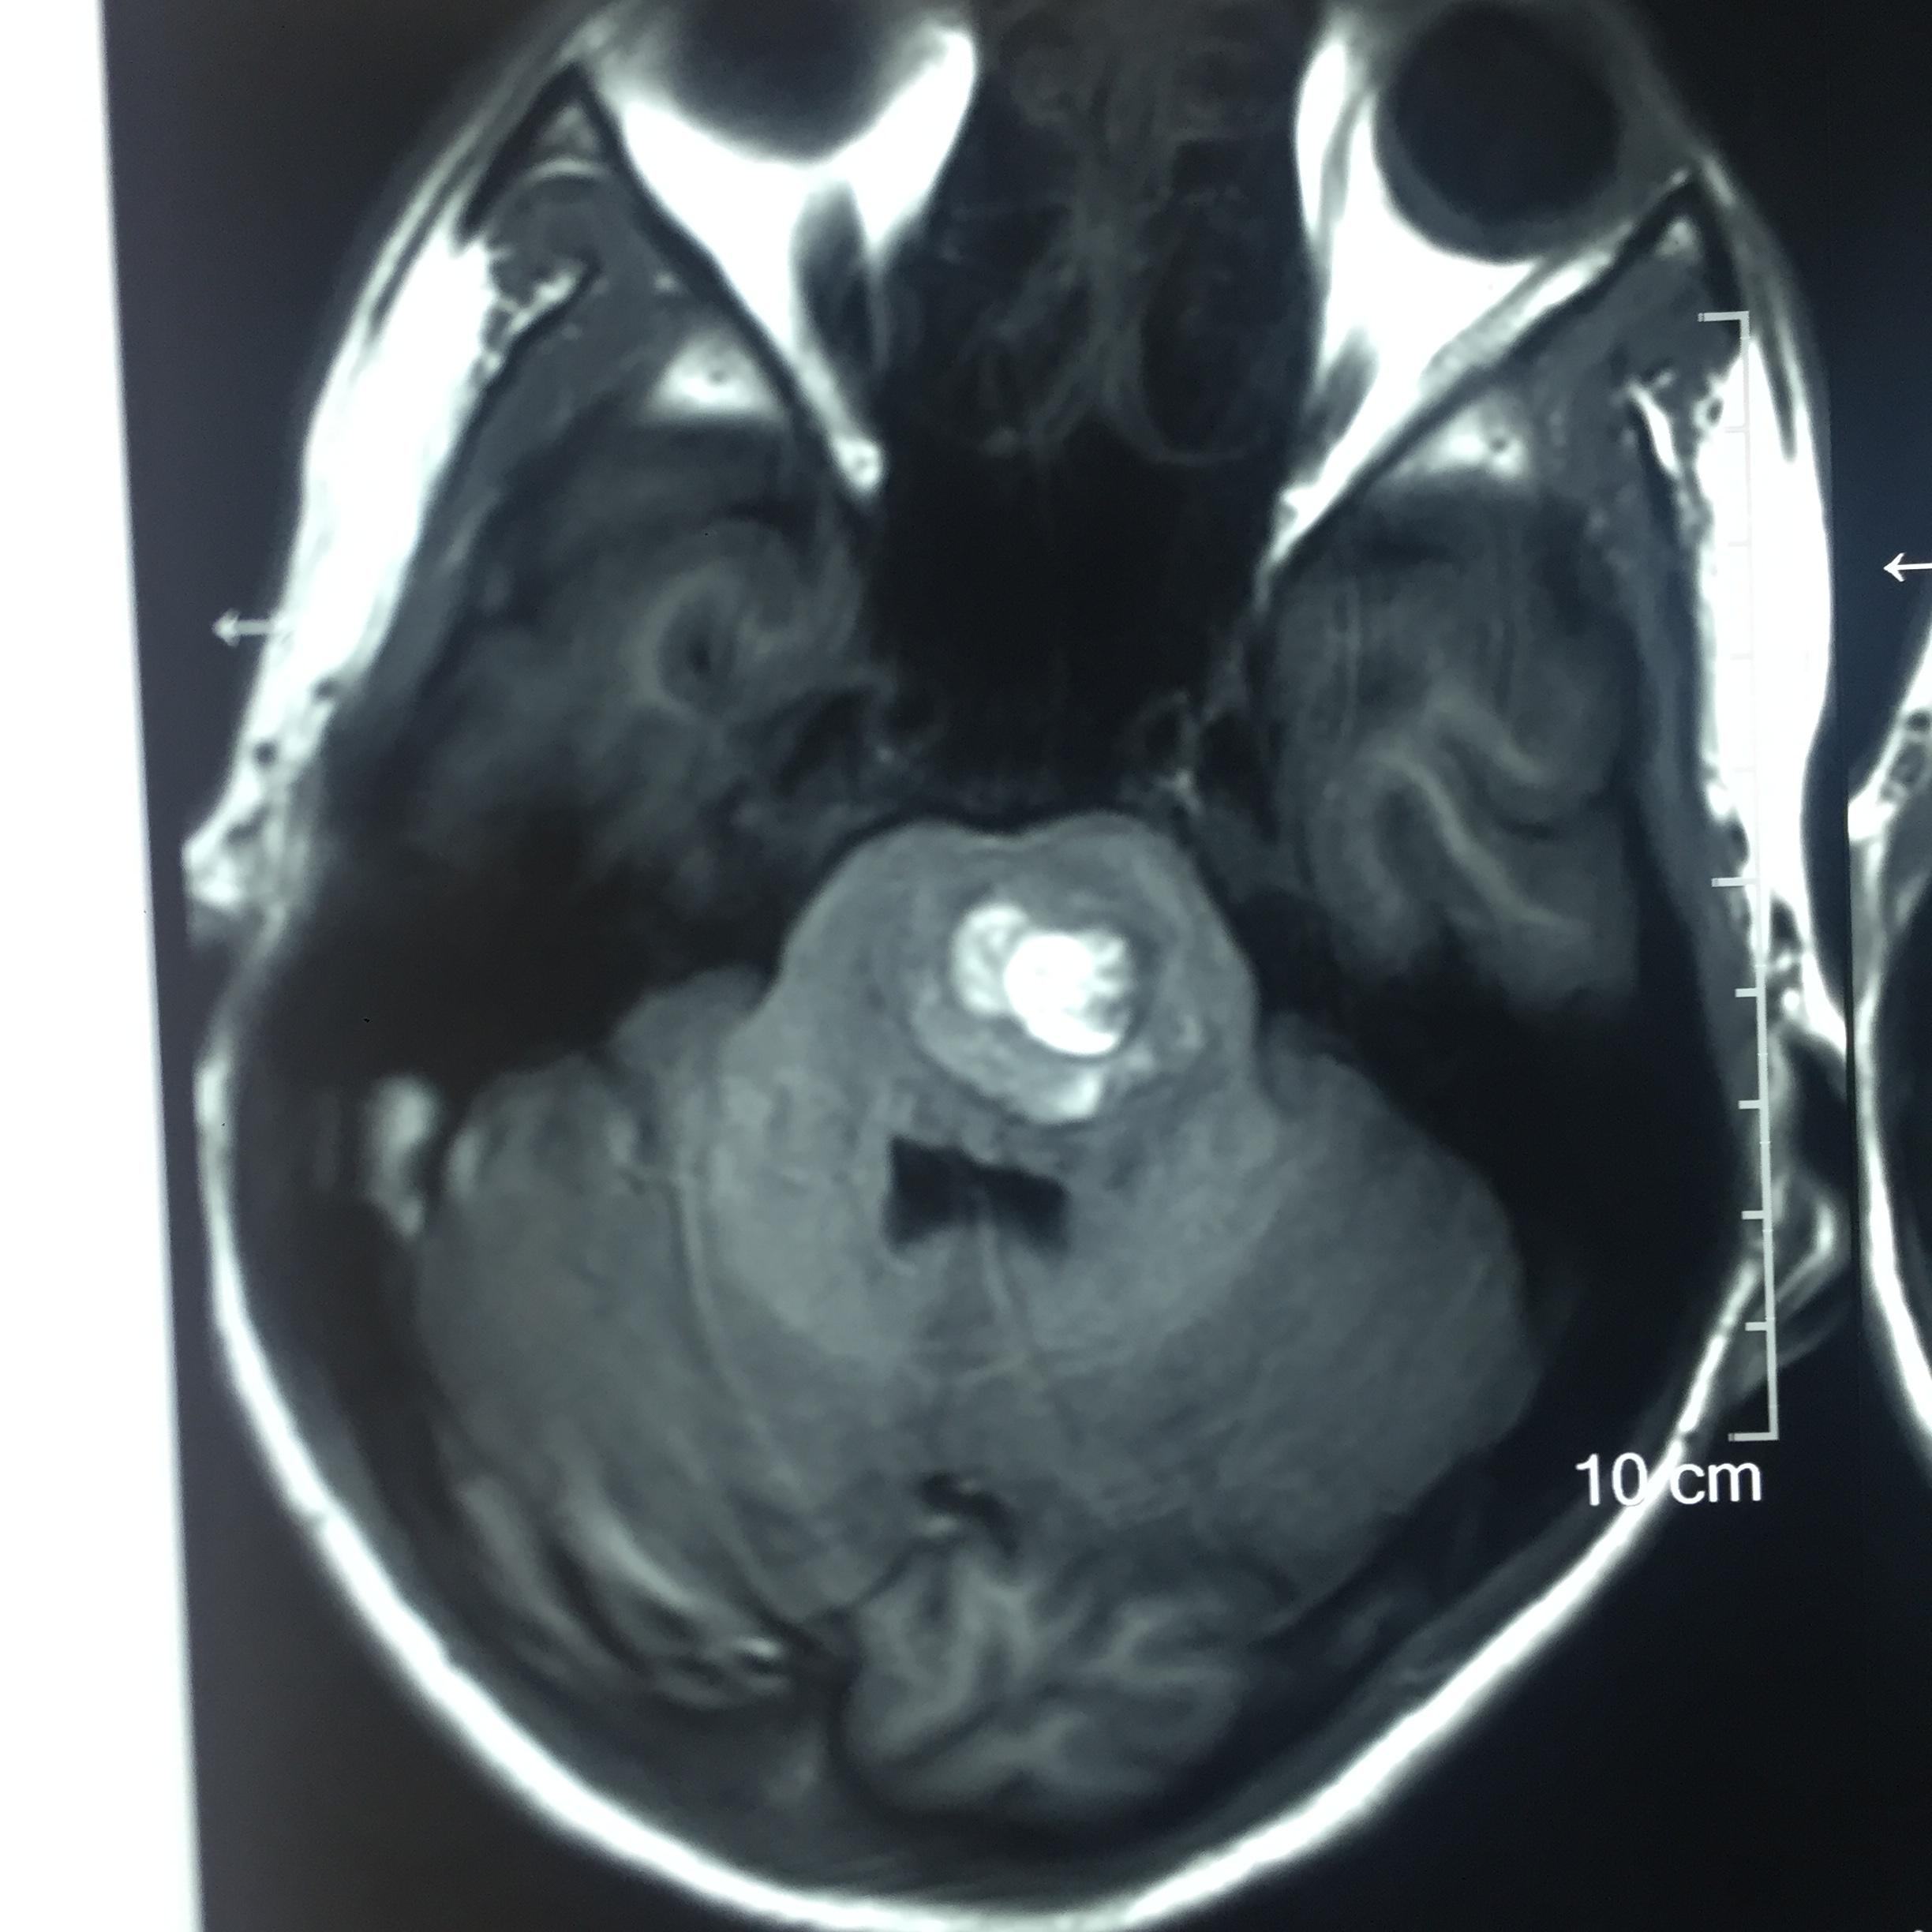

Brainstem Cavernoma : Surgery - Microsurgical excision of cavernoma